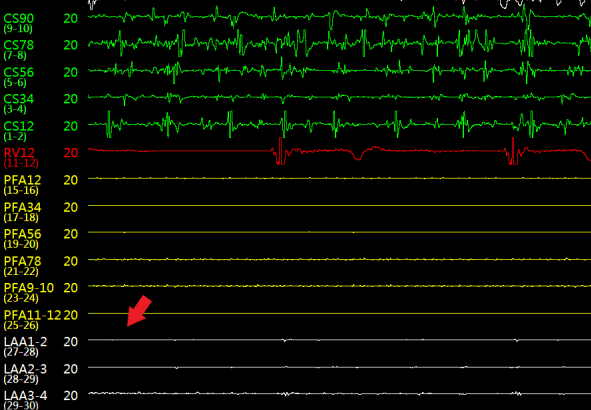

如图3所示,术中造影显示患者的左心耳固定区尺寸为23mm、深度25mm,选用规格为锚定盘直径26mm,密封盘直径 31 mm的左心耳消融封堵器植入到左心耳内。如图4-5所示,消融前后采用德诺电生理标测导管对左心耳进行电信号检测,对比结果表明左心耳电信号完全隔离;如图6所示,术者分别在左心耳消融前后进行了冠状动脉造影,造影显示回旋支无明显变化,无痉挛等不良事件发生;如图7-8所示,封堵器解脱前对左心耳消融封堵器进行了牵拉测试,器械无移位,造影及TEE超声显示左心耳完全封堵,无残余分流。

图4左心耳消融前后左心耳内电位标测

(a)左心耳消融前

(b)左心耳消融后

图5 左心耳消融前后心耳内电位对比,消融后心耳内电位消失